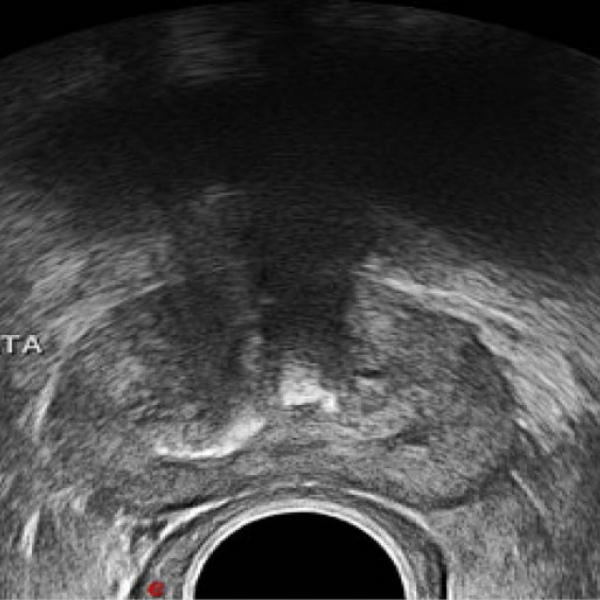

Ecografia de prostata transrectal CON biopsia Idime

INCLUYE: ECO + BIOPSIA CERRADA SUBCUTANEA + ESTUDIO PATOLÓGICO + AGUJA + ANESTESIA (BLOQUEO PUDENDO)